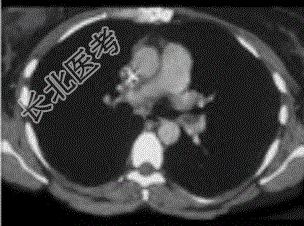

- 单项选择题患者女,51岁, 心脏手术后,突感胸痛, 结合CT图像,最可能的诊断是

A、肺栓塞

B、支气管扩张

C、肺水肿

D、肺癌

E、肺不张